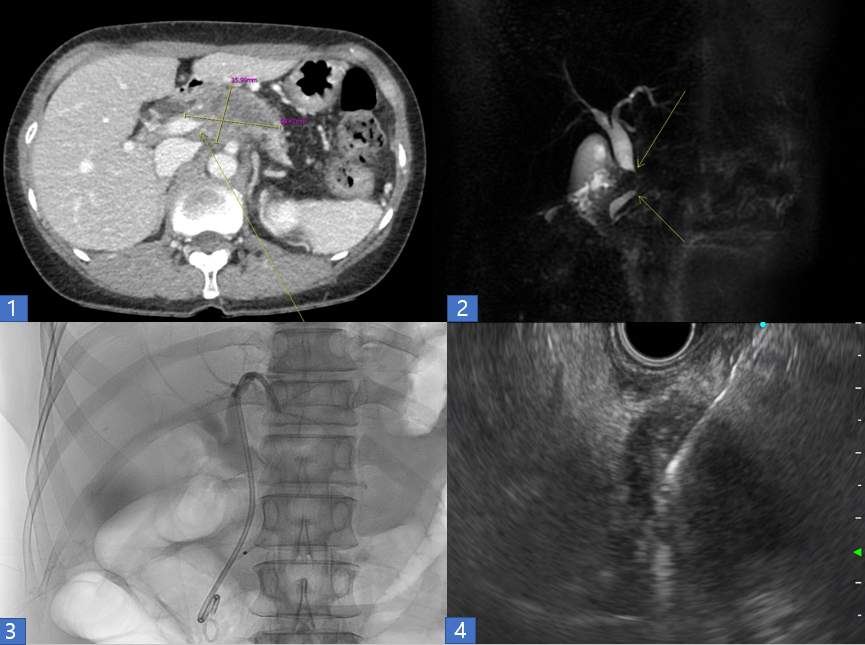

복부 CT 에서는 약 6cm 크기의 병변이 췌장에서 관찰되었습니다. 주변에 비해 색깔이 어두워 암이 의심되었고, 주변 혈관과 담관을 침범하고 있었습니다. (그림 1)

그림 1 : CT 검사에는 약 6cm 크기의 저음영의 종괴가 췌장의 목과 몸에 관찰됨.

그림 2 : MR(자기공명영상) 에서 췌장의 종괴가 담관을 막고 있음.

그림 3 : ERCP(역행성 담췌관 조영술) 을 시행하여 담관에 스텐트를 거치하여 담관이 막히지 않게 함.

그림 4 : EUS(초음파내시경) 을 통해 췌장의 병변에 대해 조직검사를 하고 있다. (하얀색의 바늘이 조직을 떼어내고 있다.)

환자분은 저를 믿고 다음날 입원을 하여 검사를 진행하였습니다. MR검사에서는 암이 담관을 침범하였고, 암은 3기이며, 혈관침범이 심해 수술을 진행하기 어려운 상황이었습니다. (그림 2) 오후에 ERCP 와 초음파내시경 검사를 시행하였고, ERCP 를 통해 담관에 스텐트를 삽입하여 황달이 생기지 않게 하였고, (그림 3) 초음파내시경 검사를 하여 췌장의 암 조직을 채취하였습니다. (그림 4)